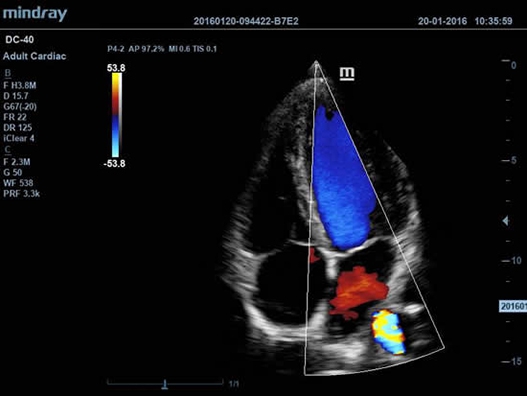

DC-40 имеет особое применение в кардиологической практике, благодаря функции Free Xros CM. Она позволяет отслеживать движения сердечной мышцы в различных фазах и одновременно определять синхронизацию миокарда. Это существенно повышает точность диагноза.

• Функции анатомического режима Free Xros M и Free Xros CM позволяют точно расчитывать анатомические параметры и отслеживать движения сердечной мышцы.

• TDI (Tissue Doppler imaging, including TDI Color, Power, PW and M mode) – пакет тканевой допплерографии, включая цветное картирование, импульсный тканевой допплер, энергетический тканевой допплер и тканевой М-режим;

• Free Xros M™ - анатомический М-режим - это возможность вращения курсора в М-режиме под произвольным углом (при фиксированном положении датчика) и, соответственно, получения графика движения структур сердца в различных произвольных плоскостях;

• Free Xros CM™ - огибающий анатомический М-режим;

• Секторный фазированный датчик Mindray P4-2